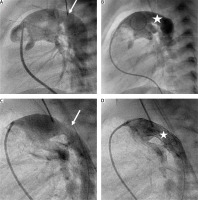

Initial percutaneous intervention, as the first stage of HP, was performed using a 6 or 7F catheter in the right femoral vein in 6 patients due to: 1) restrictive FO with BAS (n = 4), 2) intact atrial septum with septal perforation (n = 1), 3) critical aortic valve stenosis (AVS) with balloon aortic valvuloplasty (n = 2), 4) DA severe stenosis despite PGE1 infusion with Palmaz Genesis 9 mm/18 mm and 10 mm/19 mm stent deployment (n = 2). Patient 10 had a stent implanted 7 days after PAB (Figure 2).

Figure 2

Percutaneous arterial duct stent implantation. A and B in Patient 11 – Pulmonary artery angiography in lateral view showing tight pulmonary bands, mild narrowing (6.5 mm) of the arterial duct (white arrow) at the pulmonary end, and aneurysmal dilation (11.5 mm) at the aortic end. B – Pulmonary angiography following Palmaz Genesis 10 mm/19 mm stent deployment with unobturated flow (white star) and tight pulmonary bands. C and D in Patient 10 – Pulmonary artery angiography in a patient with severely stenotic arterial duct (3.5 mm) at the pulmonary end and dilation (7 mm) at the aortic end. Pulmonary arteries without bands. D – Pulmonary artery angiography following Palmaz Genesis 9 mm/18 mm stent deployment providing effective flow into the descending aorta